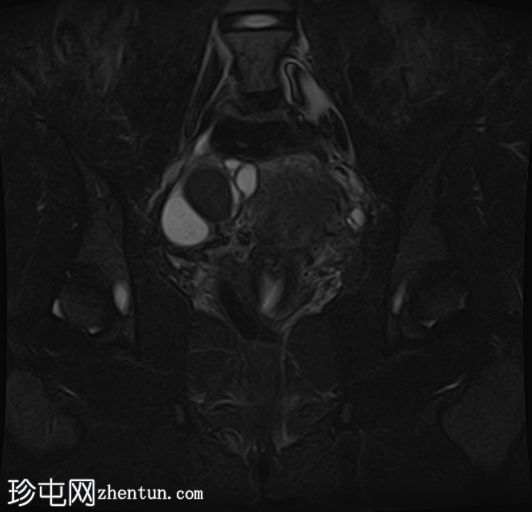

冠状位T1加权像

增强脂肪抑制像

在右侧附件区可见一较大病灶,最大轴位和头尾径约为3 x 3.8 x 3.7 cm。该病灶在T1加权像上呈高信号,脂肪抑制像上无信号抑制,在T2加权像上呈低信号(阴影效应)。病灶壁可见T2暗点征结节,增强扫描后未见明显强化。

右侧附件区可见两个较小的类似病灶,最大径约1.2 cm。

所描述的右侧附件病灶具有典型的子宫内膜异位囊肿MRI特征,包括T1高信号(无脂肪抑制)和T2低信号(阴影)。T2暗点征的存在进一步支持慢性出血性内容物。

相关的较小病灶可能代表其他子宫内膜异位种植灶。